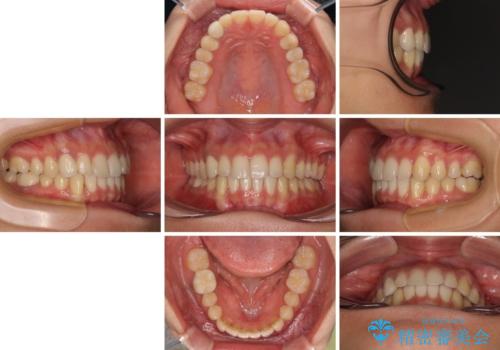

しっかりとマウスピースを装着してくださったおかげで、スムーズに治療を終えることができました。

矯正治療途中で右下奥歯の虫歯治療を近医で行ったようで、既に神経が失活していたと合わせて矯正治療後に補綴治療を行う予定です。